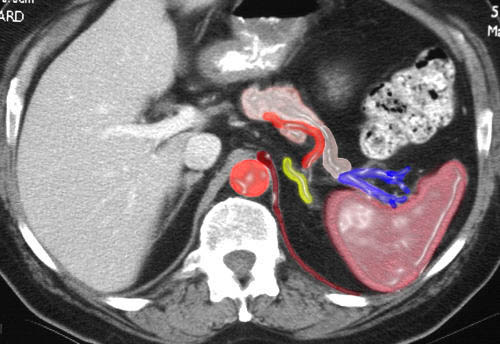

This image combines the coronal view with the axial view and reflects the intimate relationships that the adrenals have with the kidneys as well as the great vessels of the abdomen. They literally have their fingers on the pulse of the aorta (red overlay) and the inferior vena cava (IVC) (blue overlay)

This is a larger and more colorful version of the previous set. Note the relationship of the tail of the pancreas (in light pink) to the left adrenal and the medial relationship of the great vessels (“finger on the pulse”) and crura.(slithers of maroon extending from the hemidiaphragms). |

This embedded cross section reflects the true relationship of the great vessels to the adrenals. The IVC really is positioned anterior to the right adrenal while the aorta lies medial to the left. Courtesy of: Ashley Davidoff, M.D. |